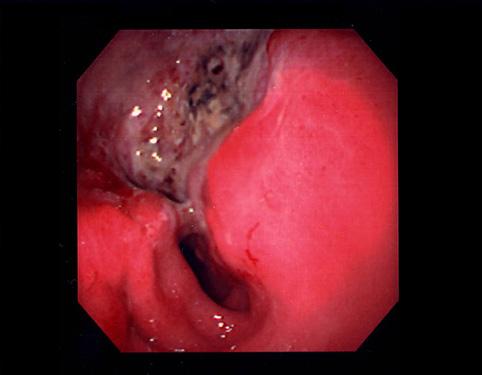

질환(병리주체)의 분류 악성 상피성종양/선암

부위(장기별) 위(부위)/전정

검사방법 내시경

종양의 육안분류 3형(궤양침윤형)/

종양의 최대경(밀리미터) 40이상

종양의 심달도 s(a)